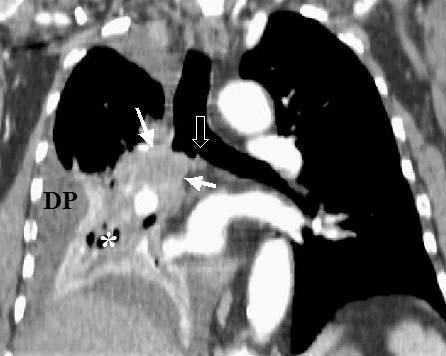

Fig. 1.--T3. (A) Reconstrucción multiplanar (MPR) de tomografía computarizada (TC) torácica con contraste con ventana de pulmón. Atelectasia completa del lóbulo inferior derecho secundario a tumor endobronquial situado a menos de 2 cm de la carina (flecha hueca). (B) La misma reconstrucción con ventana de mediastino muestra el tumor (flechas) diferenciado de la atelectasia (asterisco). Derrame pleural (DP).